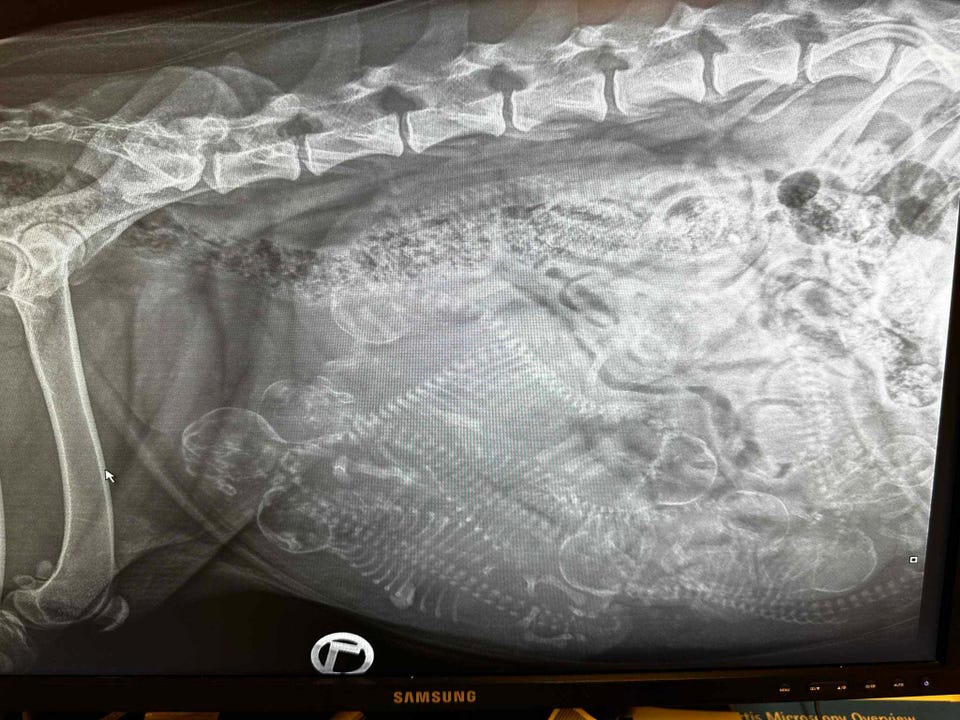

Om få dager (skrevet fredag 22.08.2025 kl. 1400) blir Kenya og Nanook lykkelige foreldre til et stort kull med malamutevalper – Team Grensefjells Enduring-kull. Ut fra røntgenbilde (vedlagt annonsen) tatt for 3 dager siden, antar/håper vi på «ca» 9 valper. Fasiten får vi forhåpentligvis i løpet av helga.